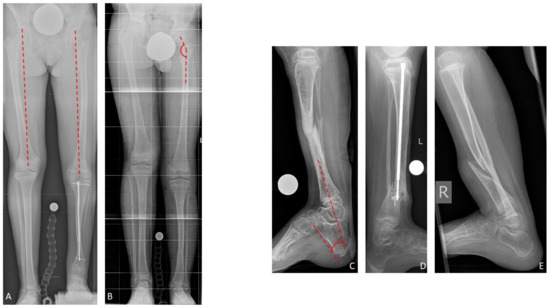

Nine of 19 patients (47%) of whom radiographs of both femora were available presented femoral overgrowth with a femoral segment which was ≥10.0 mm longer than the contralateral femur. All of them additionally showed coxa valga. In total, 17 of 21 patients (81%) with radiographs of the ipsilateral femur presented coxa valga. The mean neck-shaft angle in the study cohort was 148.1 (130–164) degrees on the leg affected by CPT, and 132.9 (119–149) on the contralateral side. Pes calcaneus was present in 16 of 24 patients (67%) in whom the tibiocalcaneal angle could be evaluated. Pes calcaneus was defined by a tibiocalcaneal angle below 60 degrees. Overall, the mean tibiocalcaneal angle measured 55.8 (23–78) degrees on the leg affected by CPT (Figure 5). The contralateral tibiocalcaneal angle could not be evaluated as lateral radiographs of the contralateral leg were not available.

Figure 5. Associated deformities: Femoral overgrowth (A), coxa valga with increased neck-shaft angle (B), and pes calcaneus with decreased tibiocalcaneal angle (CE).